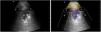

Pleuropulmonary ultrasound shows the two most frequent patterns of this respiratory pathology: 1st. “Comet tail” images or B Pattern, with unstructured pleural line, due to thickening of the interlobular septa due to inflammation (Video left). 2nd. Shred sign, characteristic of non-translobar subpleural consolidations/collections, with the shape of an inverted triangle with irregular and poorly defined edges (Video right and Fig. 2).1

ARDS lung lesions are characterized by B pattern (at least three mixed hyperechoic shadows perpendicular to the pleural line). B-Lines are not uniform and appear patchy throughout both lungs, finding normal lung tissues (denoted by the A-line) between B patterns. This distribution is known as non-uniform interstitial syndrome; existing focal changes that include mild diffuse lesions and other regions with severe damage, with shred sign and translobar consolidations, more frequent in less ventilated posterior areas around 30%–50%.2